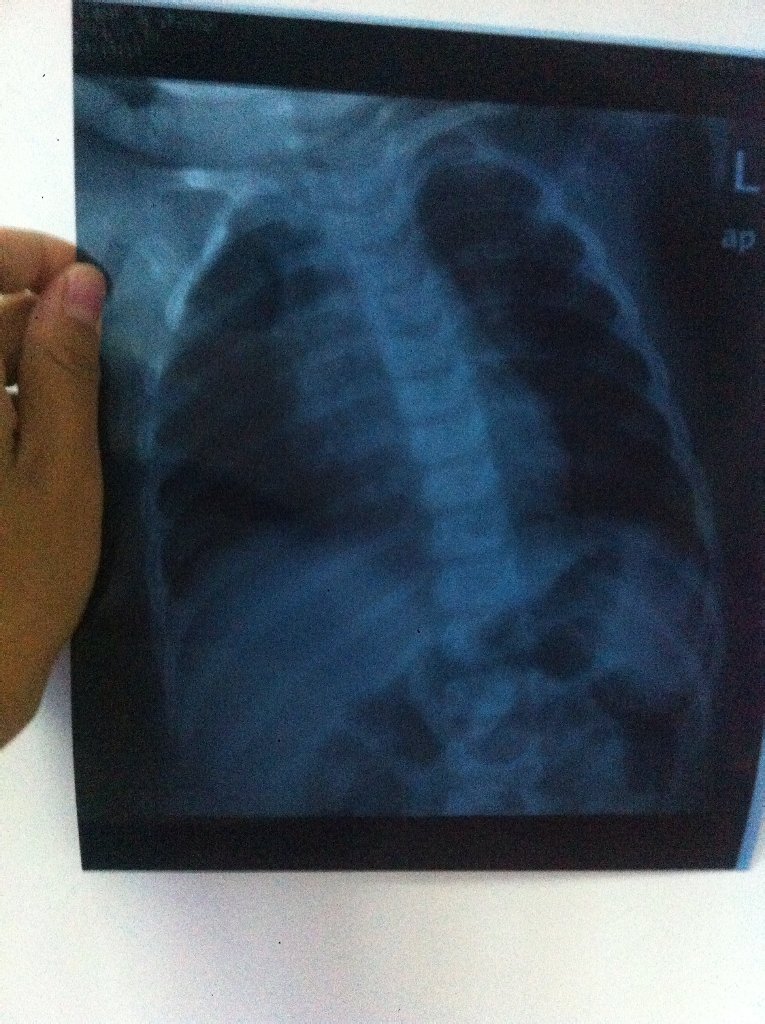

您好,肺部感染是肺炎的一种通俗的说法,新生儿肺炎一般是需要住院治疗的,因为小儿免疫力比较低,抗病能力也比较低,肺部感染不及时控制的话可以出现感染扩散,甚至出现肺炎合并心衰等情况,从而影响孩子的心肺发育和生命安全。所以最好还是及时到医院去就诊,如果确定是肺炎的话最好住院治疗。